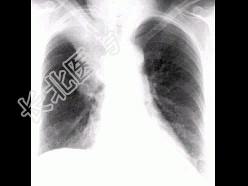

- 单项选择题男,74岁, 咳嗽,咳痰1月余, 咯血丝痰1周伴胸痛,胸片如图, 最可能的诊断为 ( )

A、右上肺浸润型肺结核

B、右上肺不张

C、右侧中央型肺癌并右上肺不张

D、右侧包裹性积液

E、右肺上沟瘤